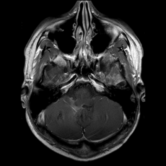

The category discovery clusters employing our LDPO method are found to be more visually coherent and cluster-wise balanced in comparison to the results in [44] where clusters are formed only from text information ( radiology reports). Fig. 4 Left shows the image numbers for each cluster from the AlexNet-FC7-Topic setting. The numbers are uniformly distributed with a mean of 778 and standard deviation of 52. Fig. 4 Right illustrates the relation of clustering results derived from image cues or text reports [44]. Note that there is no instance-balance-per-cluster constraints in the LDPO clustering. The clusters in [44] are highly uneven: 3 clusters inhabit the majority of images. Fig. 5 shows sample images and top-10 associated key words from 4 randomly selected clusters (more results in the supplementary material). The LDPO clusters are found to be semantically or clinically related to the corresponding key words, containing the information of (likely appeared) anatomies, pathologies (e.g., adenopathy, mass), their attributes (e.g., bulky, frontal) and imaging protocols or properties.

Next, from the best performed LDPO models in Table 2, AlexNet-FC7-Topic has Top-1 classification accuracy of 0.8109 and Top-5 accuracy 0.9412 with 270 formed image categories; AlexNet-FC7-ImageNet achieves accuracies of 0.8099 and 0.9547, respectively, from 275 discovered classes. In contrast, [44] reports Top-1 accuracies of 0.6072, 0.6582 and Top-5 as 0.9294, 0.9460 on 80 text only computed classes using AlexNet [27] or VGGNet-19 [47], respectively. Markedly better accuracies (especially on Top-1) on classifying higher numbers of classes (being generally more difficult) highlight advantageous quality of the LDPO discovered image clusters or labels. This means that the LDPO results have rendered significantly better performance on automatic image labeling than the most related previous work [44], under the same radiology database. After the subjective evaluation by two board-certified radiologists, AlexNet-FC7-Topic of 270 categories and AlexNet-FC7-ImageNet of 275 classes are preferred, out of total six model-encoding setups. Interestingly, both CNN models have no deep feature encoding built-in and preserve the gloss image layouts (capturing somewhat global visual scenes without unordered FV or VLAD encoding schemes [9, 8, 21].).